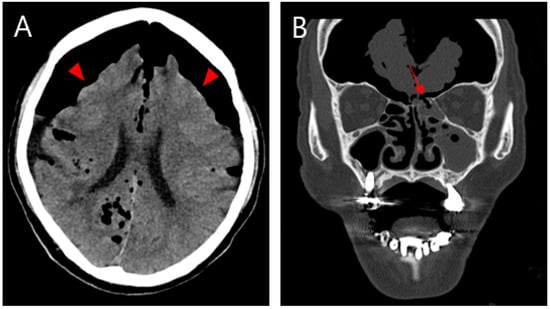

Tension Pneumocephalus Caused by Ethmoidal Roof Fracture: Emergent Surgical Decompression